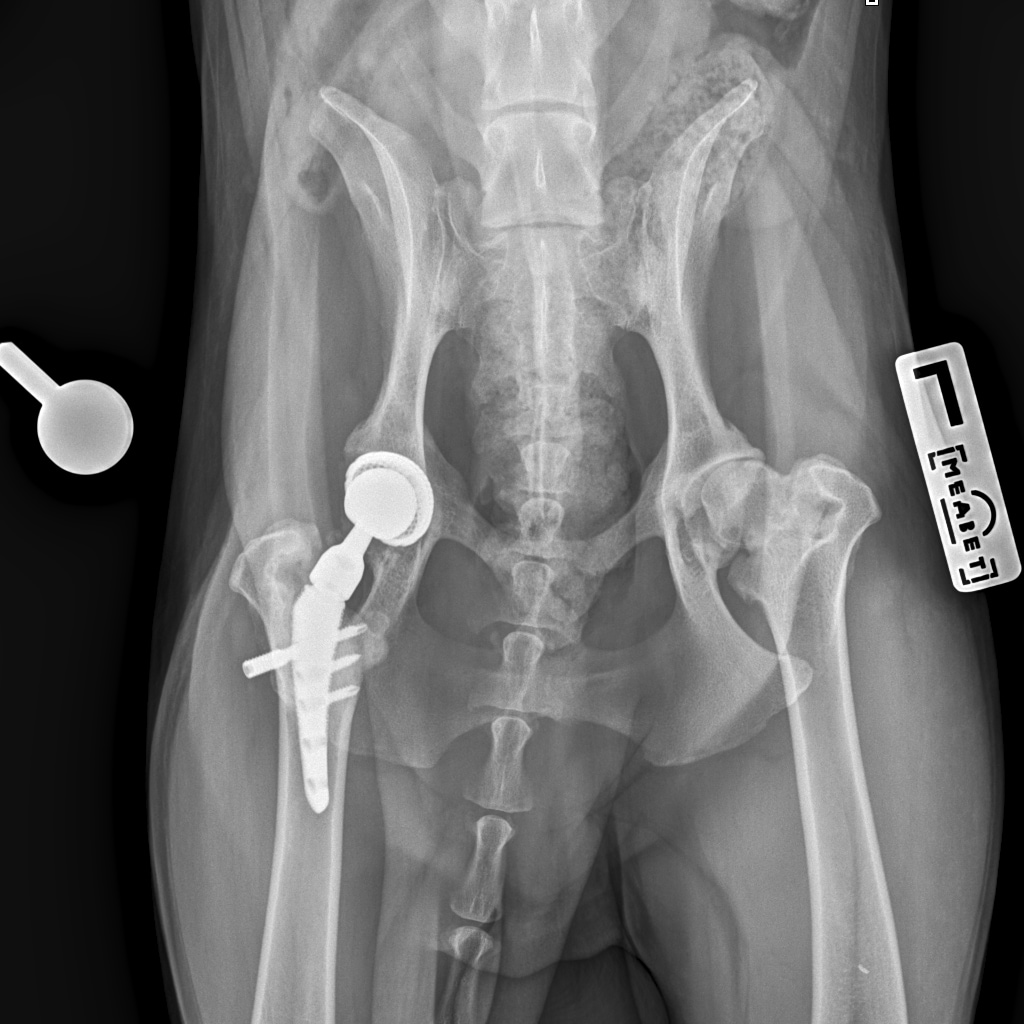

26 августа к 10 утра голодными, нас ждут на контрольный рентген в клинике на Вернадского.

Рентген будет под седацией

За время противовоспалительной терапии снизилось воспаление и в левом тазобедренном суставе, но увы, форма головки бедренной кости и состояние шейки бедра , лучше не стали:(((

Операция однозначно нужна.

Снимки столь качественные, что их можно в учебник

Железный дровосек